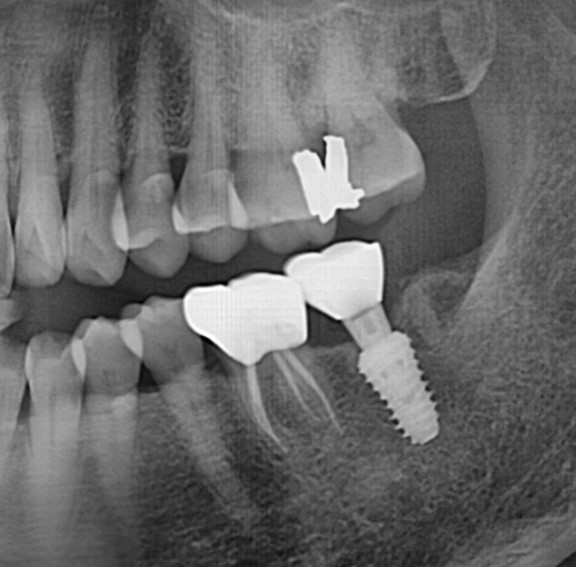

수술 전

수술 후

완전매복치사랑니 발치 + 구치부 임플란트 사례

전후사진